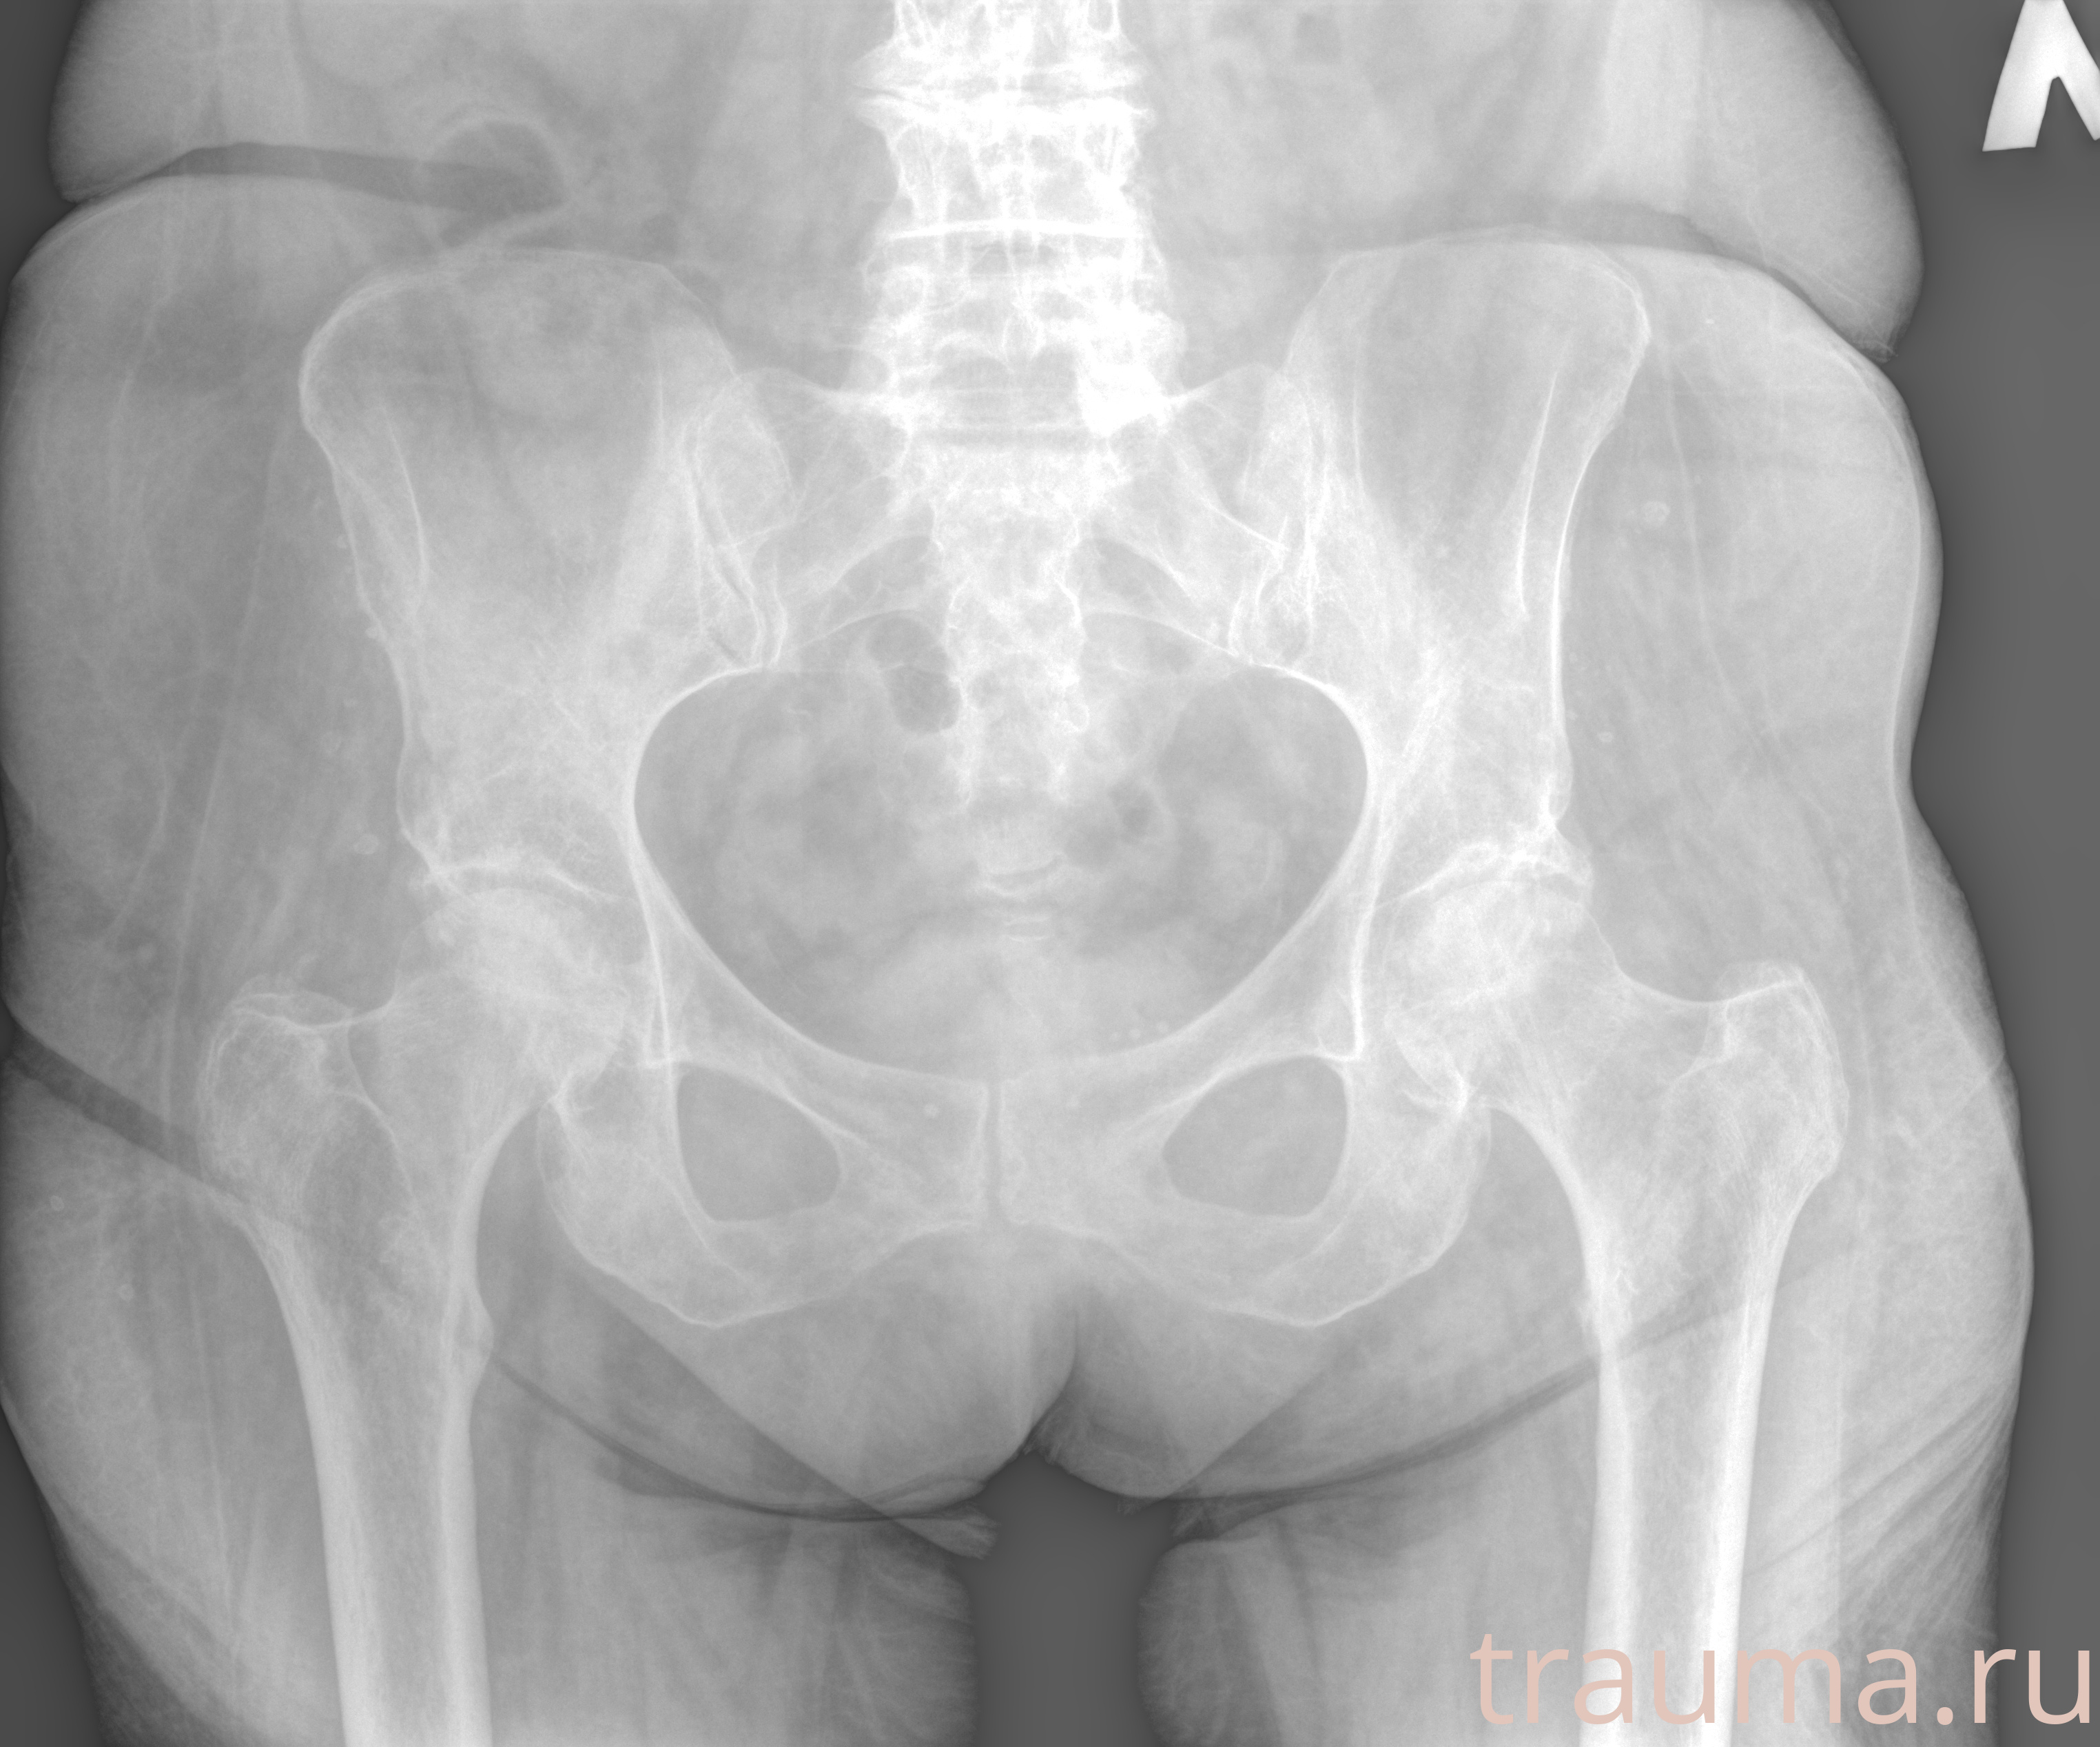

Рентгенограммы

Рентген на дому: по вашему адресу приезжает врач-рентгенолог, травматолог-ортопед с мобильным рентгеновским аппаратом, проводит диагностику травмы или заболевания, делает необходимые рентгенограммы, дает рекомендации по дальнейшему лечению. Получить качественные снимки в домашних условиях возможно благодаря уникальной методике, разработанной МосРентген Центром для института  Склифосовского